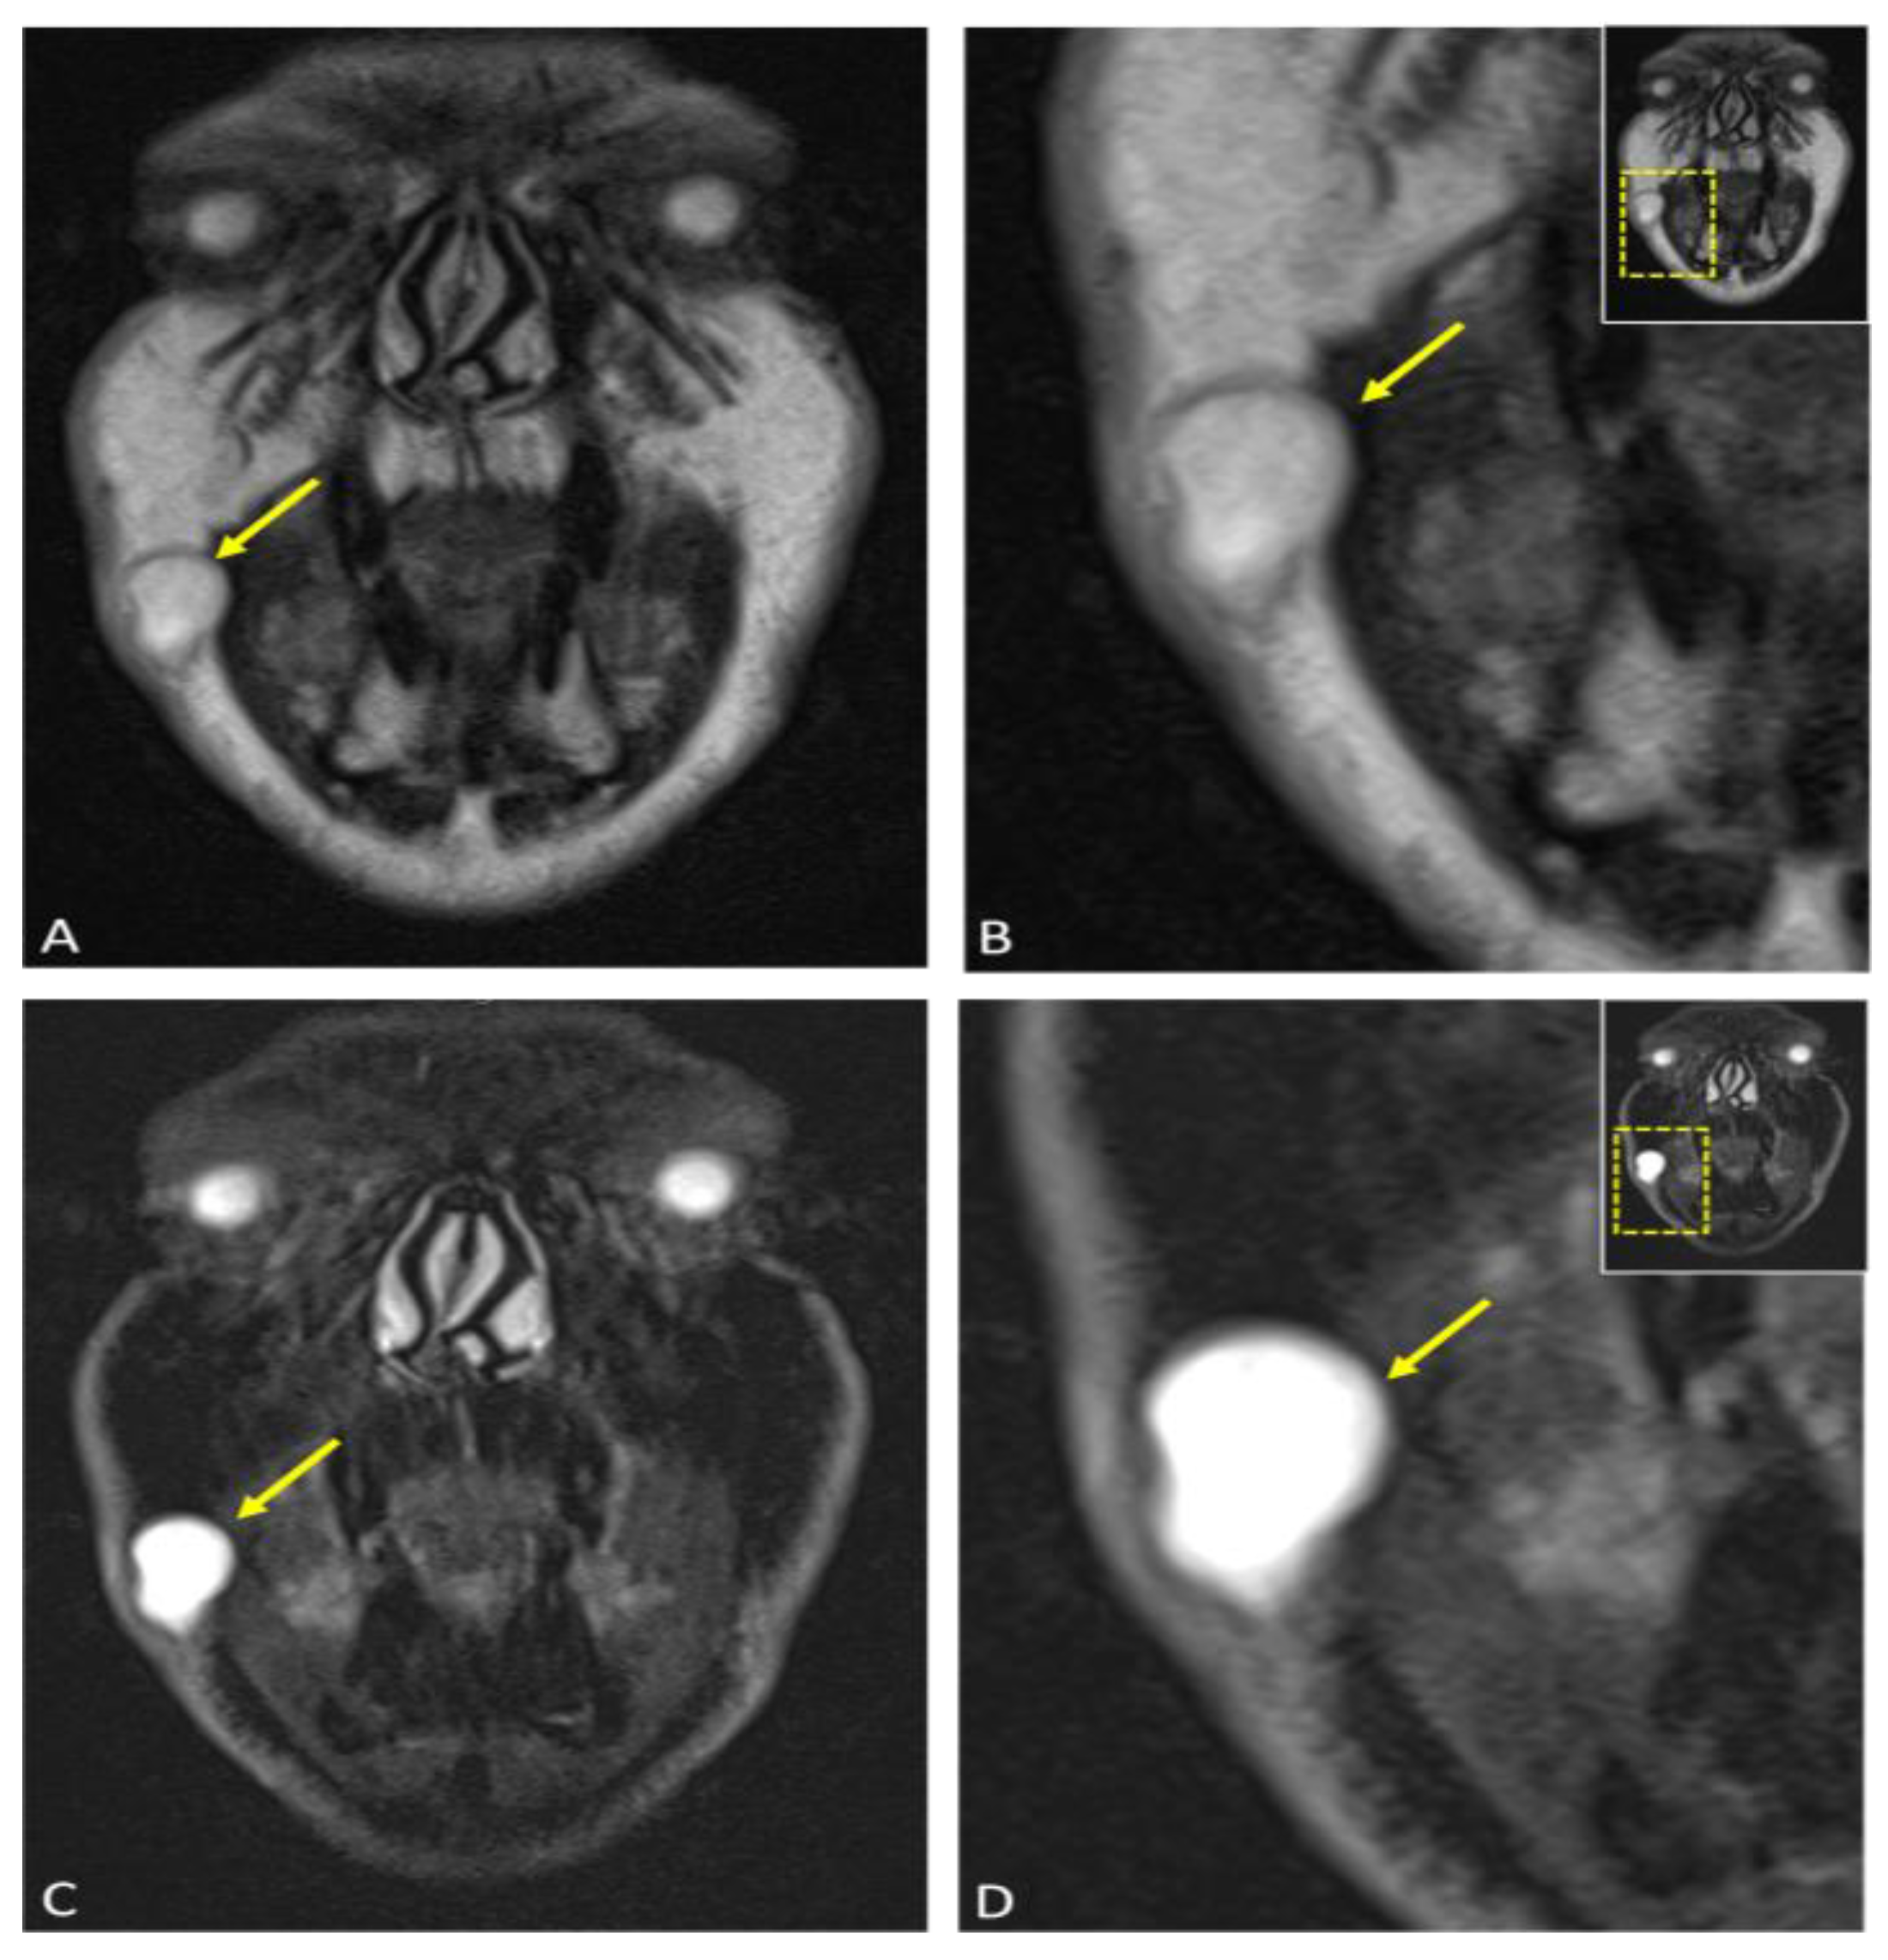

Coronal reconstructions of the lesion (arrow) are displayed in (A) T2-weighted Dixon MRI in-phase (water + fat) and (C) T2-weighted Dixon MRI water-only phase, which can be used as a fat-suppressed image. Enlarged views of the lesion are provided in (B,D) for greater clarity. The imaging findings are consistent with an epidermoid cyst, characterized by a well-circumscribed appearance and lack of infiltration into adjacent structures or inflammatory changes.